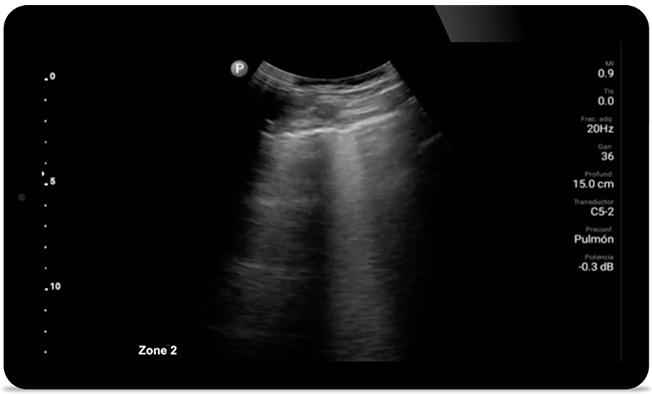

Следите за COVID-пневмонией

Lumify может помочь получить результаты, схожие с КТ грудной клетки, при оценке пневмонии и респираторного дистресс-синдрома взрослых.